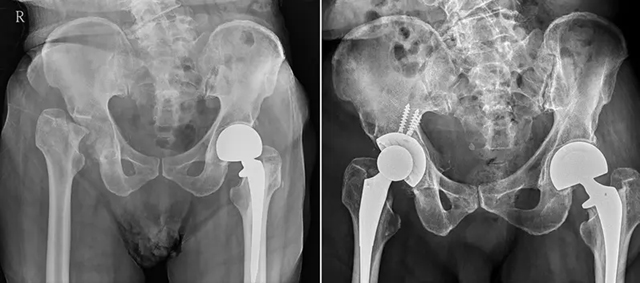

77岁男性跌倒后股骨颈断裂,导致长短脚且不良于行。患者术后疼痛明显改善,再经复健,目前已能正常行走。(图/澄清医院中港院区提供)

一名77岁男性一年前在家里不慎跌倒,起初仅是臀部隐隐作痛,没想到竟有长短脚,严重到不良于行才求医。骨科医生诊断发现,该患者因跌倒而造成右脚股骨颈断裂,碎骨嵌入骨盆与髋臼关节,关节内已充满碎裂骨头,情况复杂,所幸经人工全髋关节置换手术,才恢复双脚同长,能好好走路。

台湾澄清医院中港院区骨科医生洪舜奕说,经骨科检查与影像学确认,发现患者的右脚股骨头早已断裂并陷入髋臼关节腔内,导致双脚长短相差达四公分,研判一年前跌倒时就发生了股骨颈骨折,但未被正确诊断,导致长期错位与骨坏死,碎骨嵌入骨盆与髋臼关节,因而饱受疼痛与关节受限之苦。

经人工全髋关节置换手术时,为他取出关节内碎裂的骨头、沾黏的软组织,重建髋臼与股骨之间的稳定关节,并将腿长恢复至正常长度,患者术后疼痛明显改善,再经复健,目前已能正常行走。

澄清医院中港院区骨科医生洪舜奕诊研判,患者1年前跌倒时就发生了股骨颈骨折,但未被正确诊断。图/澄清医院中港院区提供